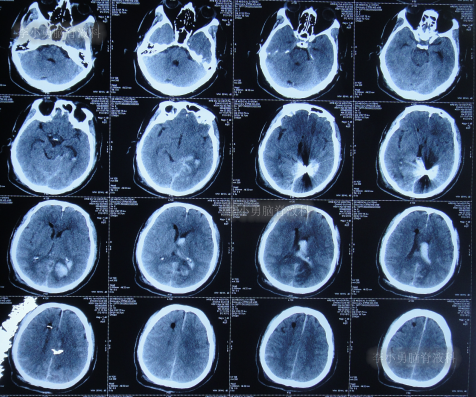

抗感染治疗28天即2022年5月25日,查头颅CT示仍脑积水(图-6),脑脊液仍有细菌。

图-6:2022年5月25日头颅CT

抗感染治疗41天即2022年6月7日,脑脊液化验细菌消失,但查头颅CT示仍脑积水(图-7)。

图-7:2022年6月7日头颅CT

2022年6月8日(第2次住院治疗44天),按计划进行了脑室腹腔分流术。

2022年6月13日(脑室腹腔分流术后5天),术后患者仍走路不稳,有时胡言乱语,言语不清,小便失禁,查头颅CT(图-8)示脑室仍有扩张。

图-8:2022年6月13日头颅CT

2022年6月17日(分流术后9天即第2次该院治疗53天),查头颅CT虽仍有脑积水(图-9),但仍让患者出院,出院时:仍走路不稳,有时胡言乱语,言语不清,小便失禁;转至当地的某医院进行治疗。

图-9:2022年6月17日头颅CT